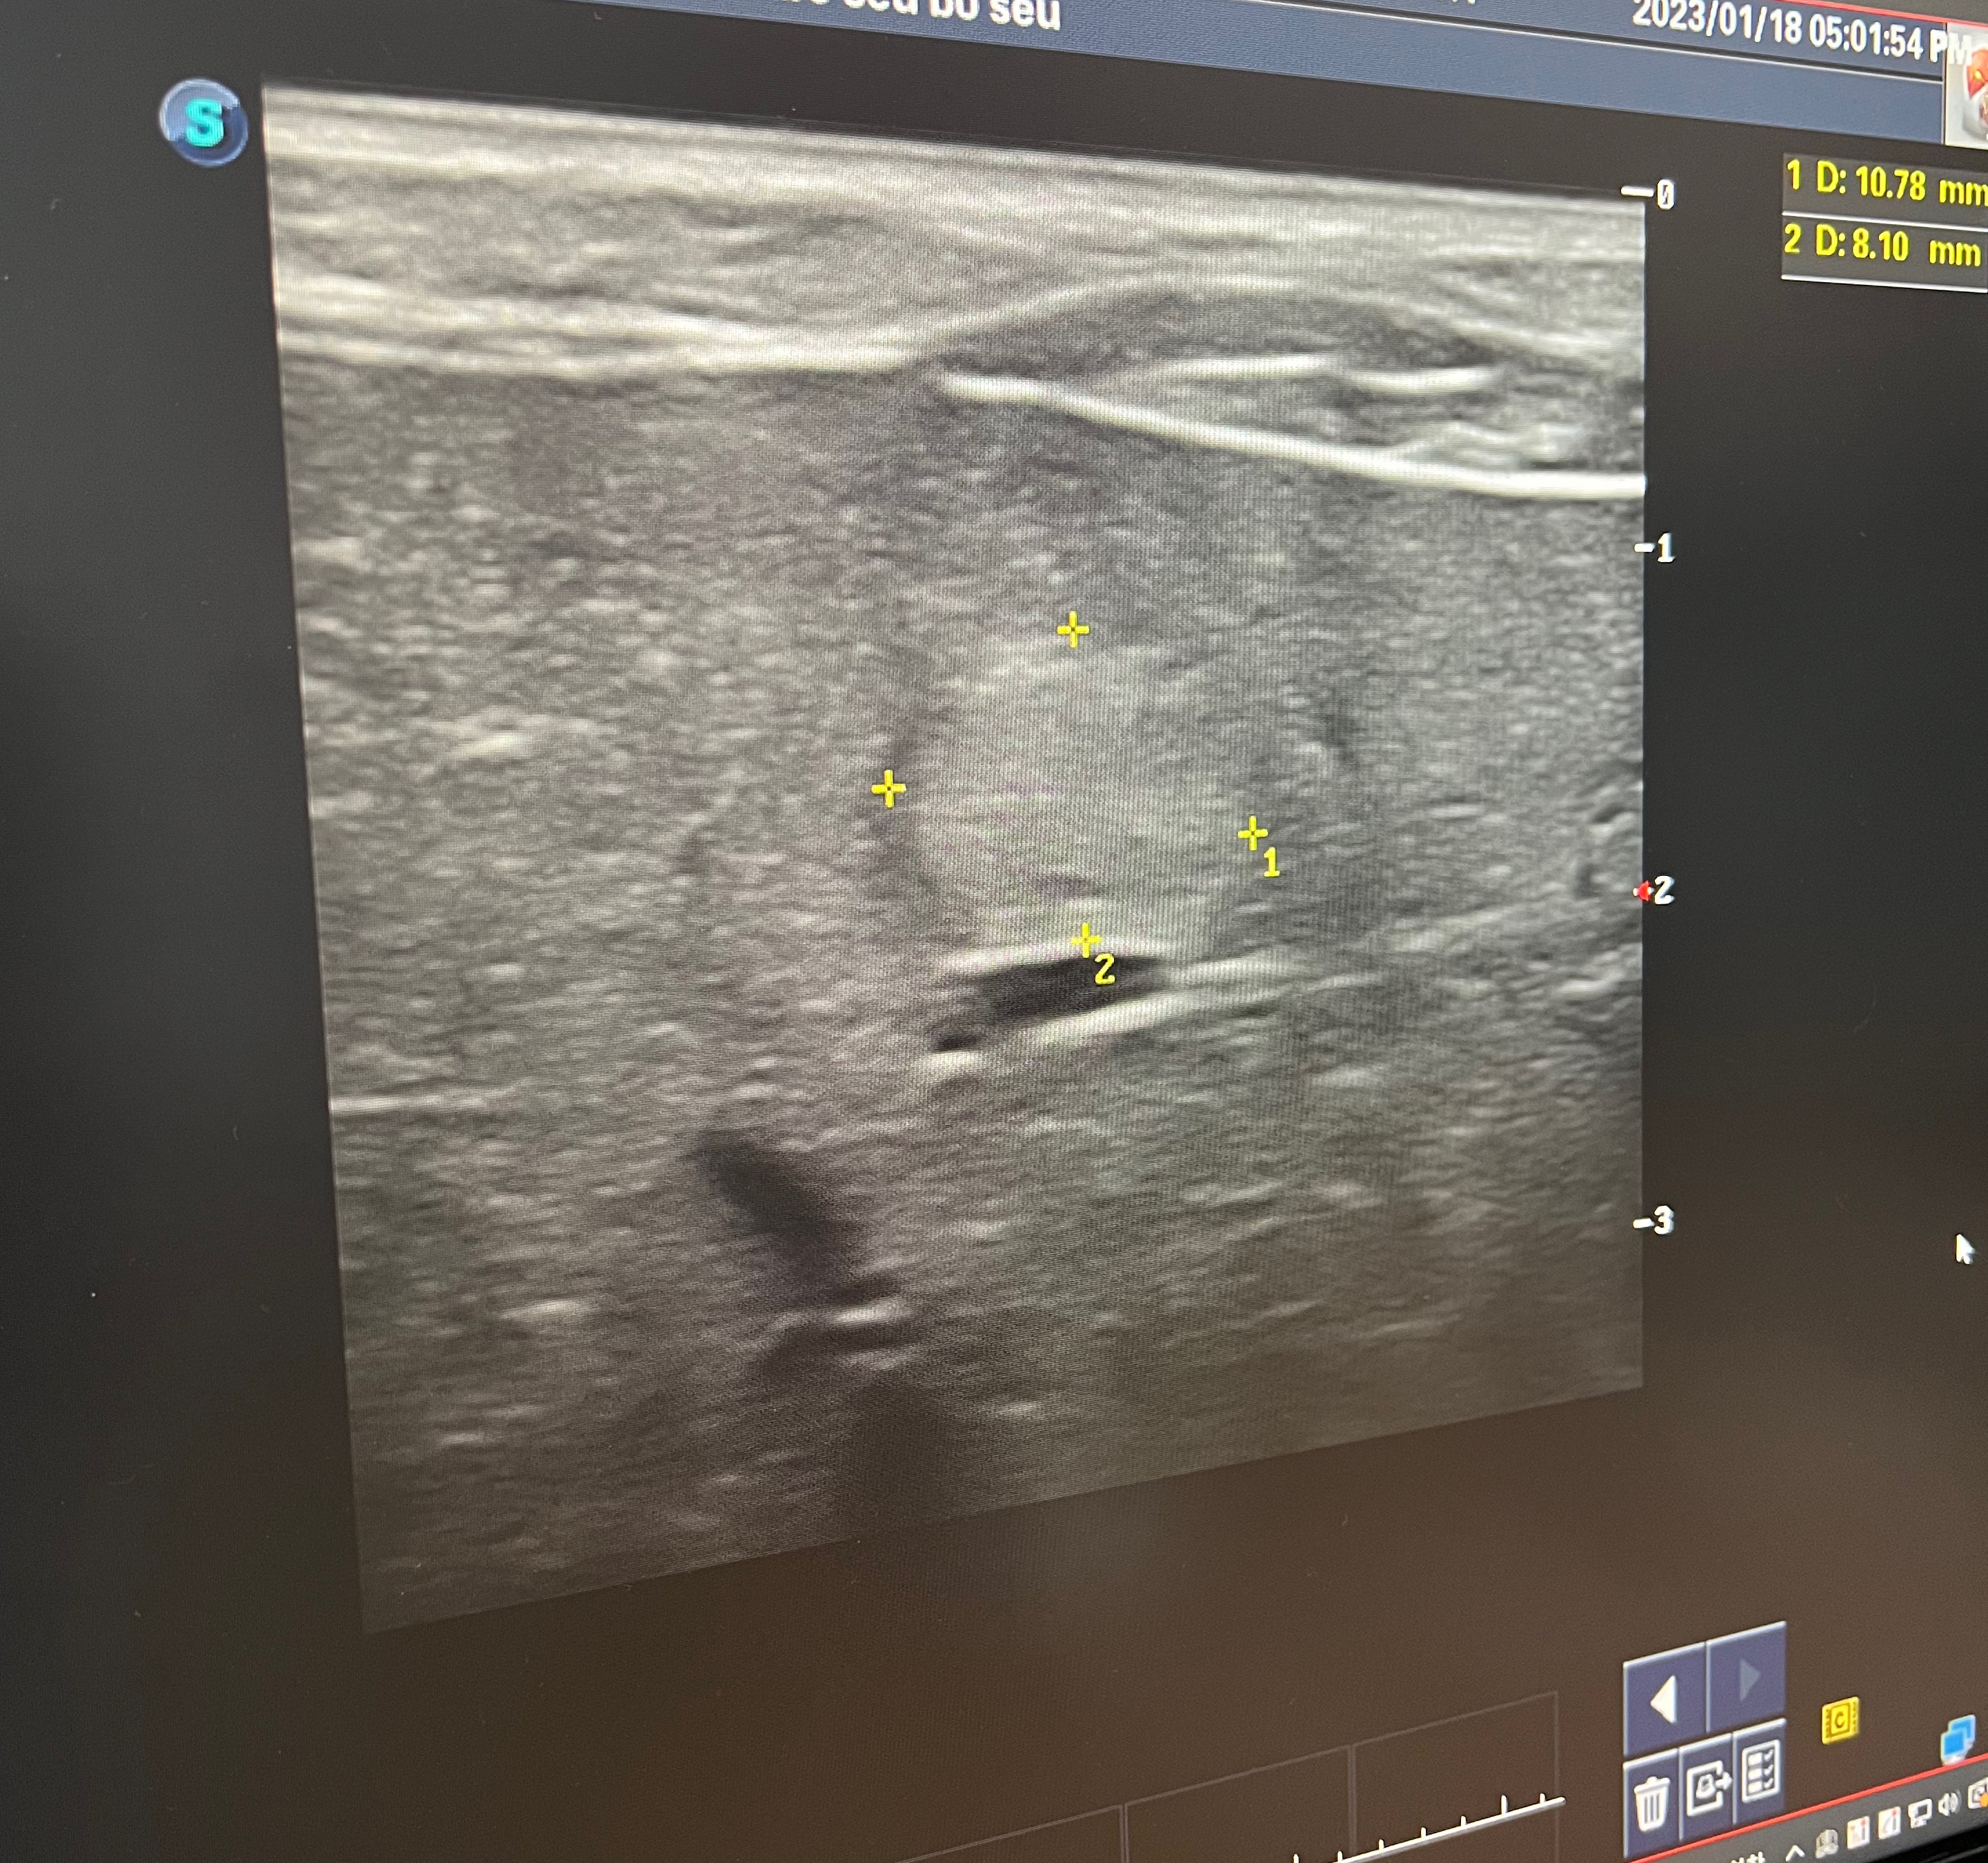

초음파 검사결과 이런것이 발견되었는데 뭔지 알려면 ct 검사, 검체 체취를 해야한다고 합니다. 그런데 체취하려면 마취를 해야하는데 간수치가 높아서 마취는 힘들다 하십니다.